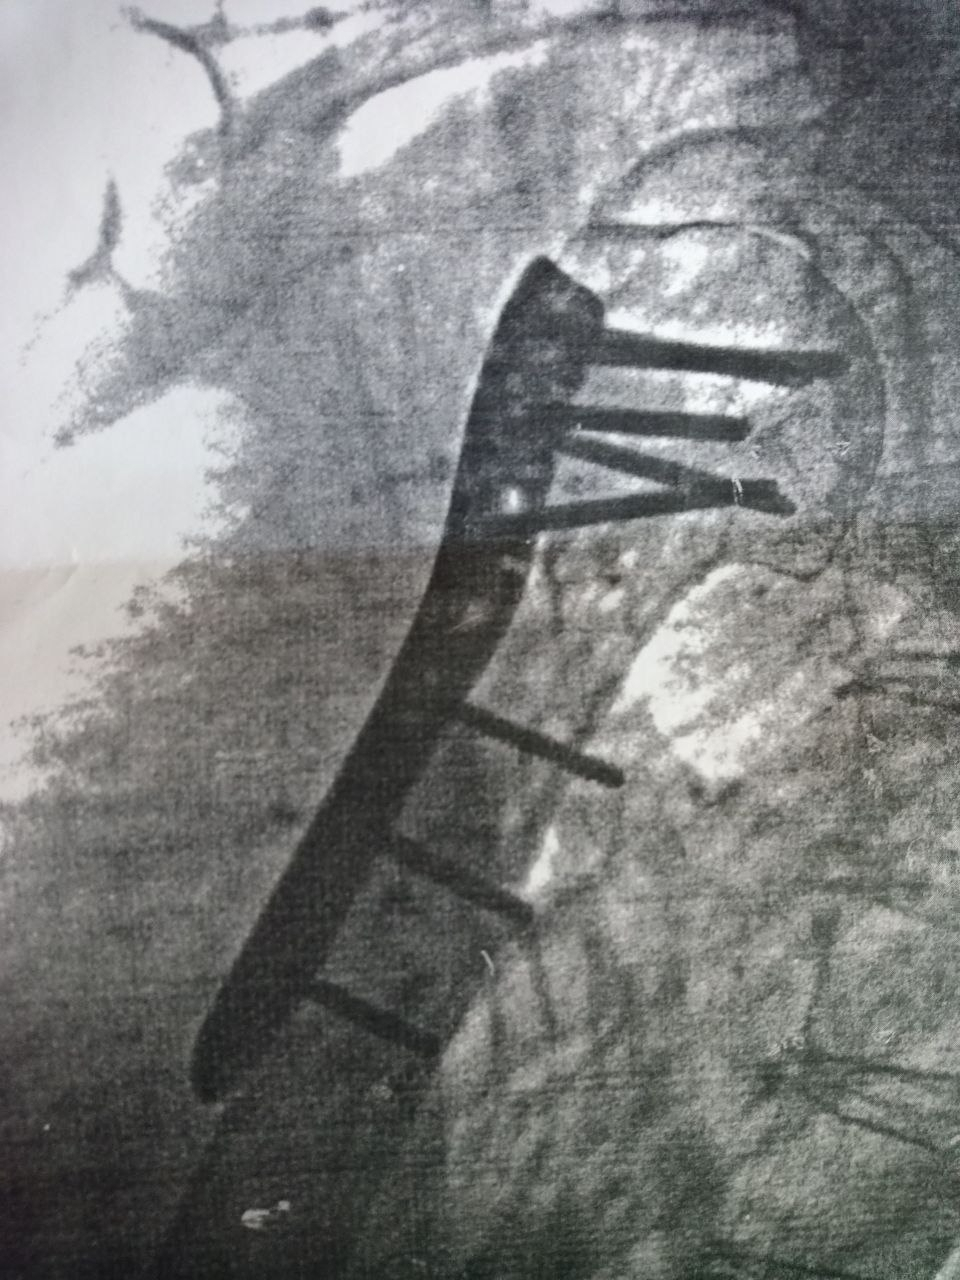

В сухом остатке - вырезан кусок предплечья с некротизировавшимися тканями, зашито, заживает. Перелом хирургической шейки плеча, перелом большого бугорка плечевой кости со смещением (оторвался он нахрен, я видела красивые фоточки), собрано на пластине.